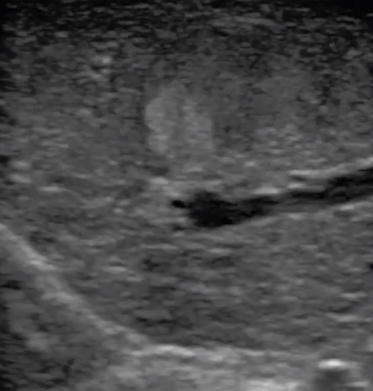

腹腔鏡下 肝臟占位